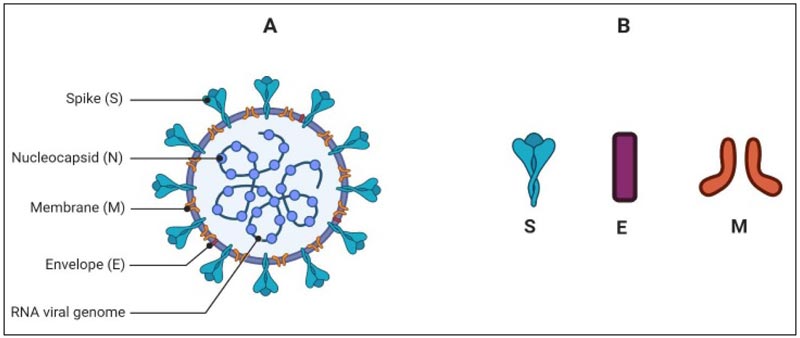

Special Issue 2: Oral Health, Dentistry and COVID-19 Pandemic

Edited by: Quazi S. Zahiruddin

July 12, 2021

Quazi S. Zahiruddin, Gaurav Mishra, Manoj Patil, Akhilesh Aggrawal and Abhay Gaidhane

Gargi C. Nimbulkar, Kumar G. Chhabra, Shravani Deolia and B Unnikrishnan

Amit Reche, Anjali Nandanwar, Aniket Hedaoo, Kumar G. Chhbra, Punit Fulzele and Gargi Nimbulkar

Nidhi Motwani, Anuja Ikhar, Manoj Chandak and Shailesh Gondivkar

Priyanka Jaiswal, Pankaj Banode, Diksha Agrawal, Pavan Bajaj, Deepika Masurkar and Amol Gadbail